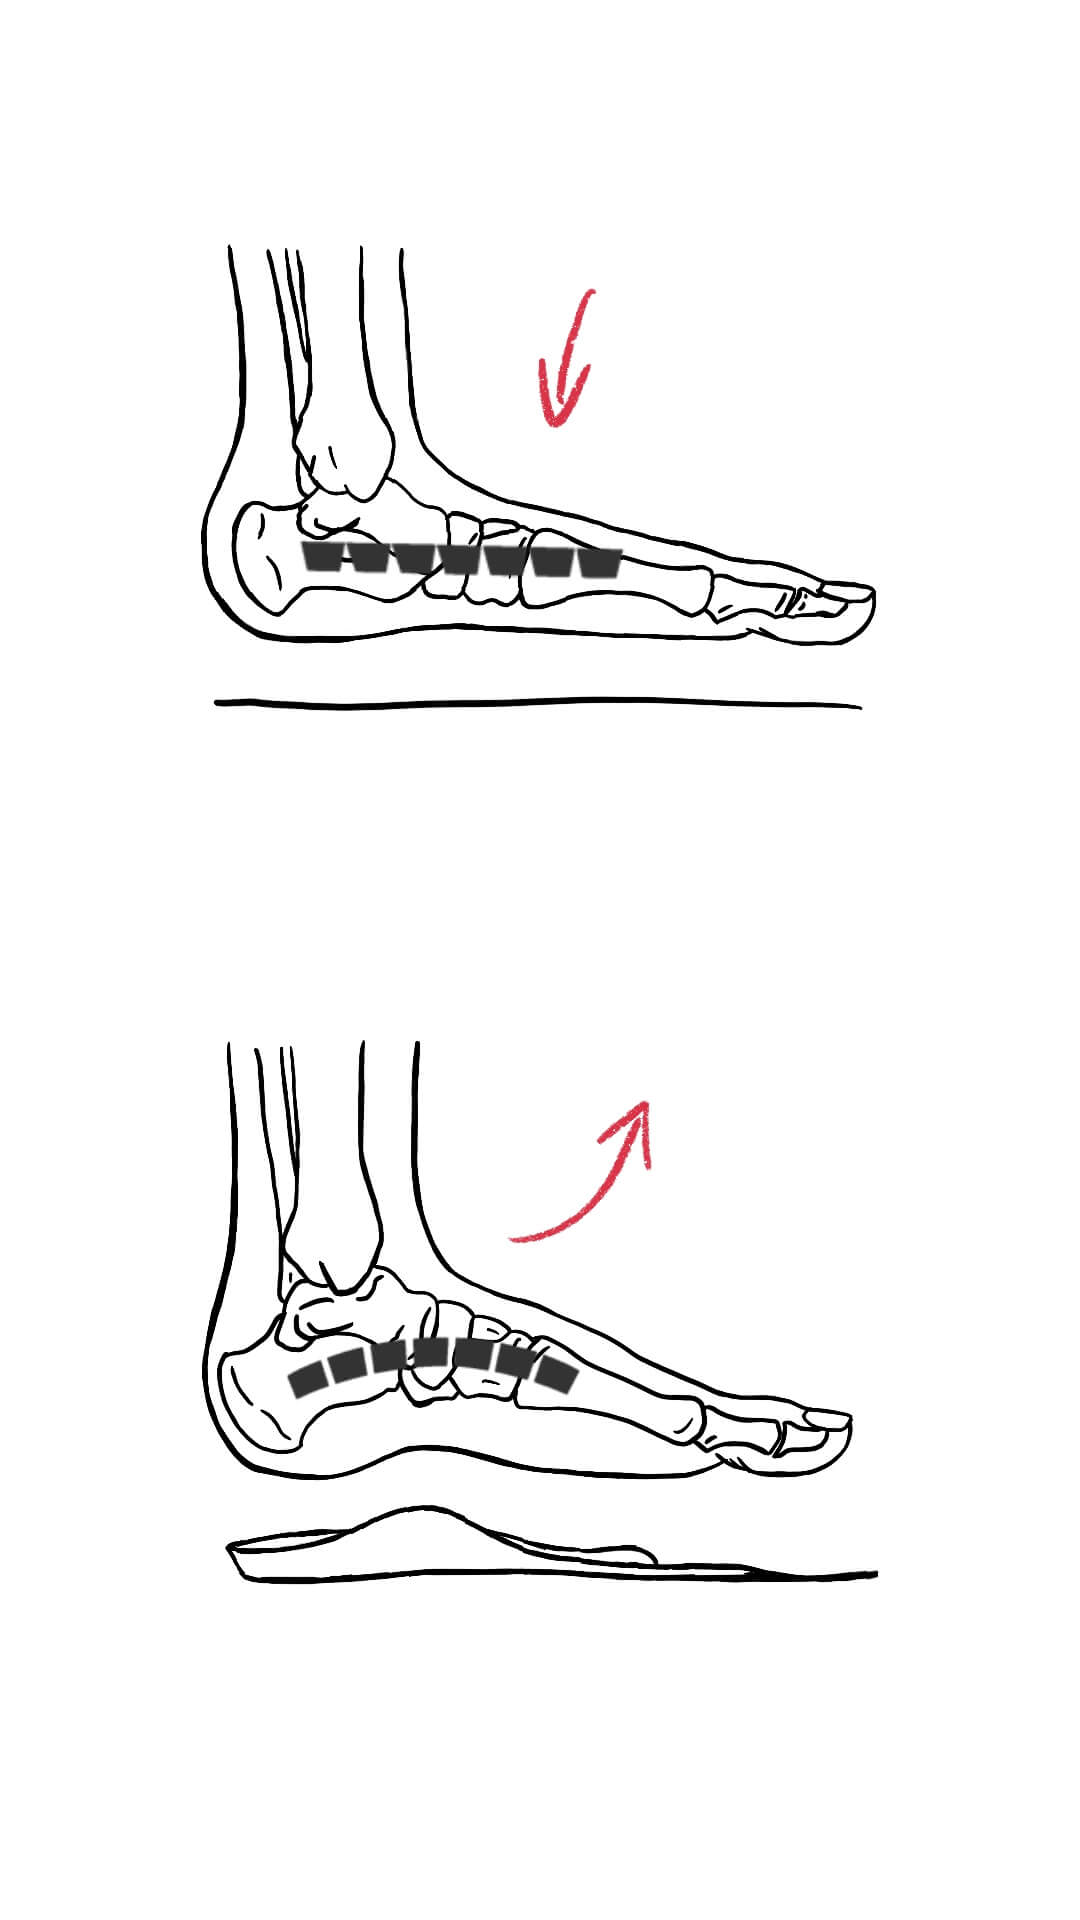

Der Hauptfaktor, der zur Entwicklung eines Fersensporns beiträgt, ist die chronische Belastung des Fußgewölbes und der Fersenregion. Dies kann auf eine Reihe von Ursachen zurückzuführen sein, einschließlich Übergewicht, Alterung, unsachgemäßes Schuhwerk, intensives Gehen oder Laufen und bestimmte Fußfehlstellungen wie Senk- und Plattfüße oder ein hohes Fußgewölbe.

- Fußfehlstellungen: Bestimmte Fehlstellungen an den Füßen wie Plattfüße, Senkfüße und ein erhöhtes Fußgewölbe können die Art und Weise verändern, wie das Gewicht auf den Füßen verteilt wird, was wiederum die Plantarfaszie zusätzlich belasten kann. Auch können Fehlstellungen die Belastung der Sehnen und Bänder erhöhen. Beim Senk- und Plattfuß zum Beispiel, erhöht sich der Zug auf die Plantarsehnen und damit auch auf die Anteile, die an der Ferse ihren Ursprung haben. Genau da, wo der Fersensporn dann entsteht.

Die oben genannten Faktoren führen häufig zu einer Überdehnung, Reizung und Entzündung der Plantarfaszie, einem breiten Band aus Bindegewebe, das die Ferse mit dem Vorderfuß verbindet. Wenn dieser Zustand über einen längeren Zeitraum anhält, kann dies dazu führen, dass der Körper zur Ausheilung der Mikroverletzungen Kalk ablagert, was zum Wachstum eines Knochensporns an der Unterseite der Ferse führt.